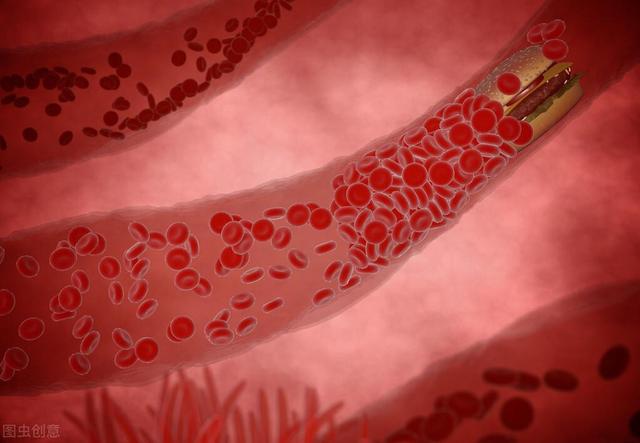

- a. 動脈硬化:これが最も一般的な原因である。脳につながる動脈の開存性と脳内の動脈の開存性の両方に影響を及ぼす。頸動脈は脳に血液を供給する最も重要な動脈のひとつである。アテローム性動脈硬化症は頸動脈にプラークを形成する。アテローム性動脈硬化症は頸動脈にプラークの形成をもたらし、プラークの形成は血管の内腔の狭窄をもたらし、内腔の狭窄は脳への血流不足をもたらす。

動脈硬化は全身の動脈に影響を及ぼすが、脳内の動脈は免れない。その結果、脳への血流が悪くなり、脳内の血流も悪くなる。二重の影響が脳への血液供給に影響し、脳への血液供給が不足する。動脈硬化は高齢者の血液供給不足の最も重要な原因である。

血管が原因。血管壁の損傷、内腔の狭窄、血管攣縮などである。脳動脈硬化、壁に硬化したプラークの形成、内腔の狭小化、菲薄化、血管抵抗の増大による血流量の減少、特に脳を長時間にわたって酷使し続けた後に、脳血液の供給と相対的に起こることが多い。

血液に関する原因。血液化学の変化、粘性の増加。例えば、赤血球増加症、高脂血症、脱水症、血液量の減少による血流の停滞はすべて、脳への血液供給不足の素因となる。

2、高脂血症高脂血症、特に高LDL、高コレステロールの患者における最も重要な危険性は、動脈硬化を引き起こし、血管の内壁にプラークが形成されることである。

3、糖尿病糖尿病は細い血管と微小血管病変を引き起こし、脳への血液供給不足の基礎ともなる。糖尿病は糖代謝異常だけでなく、脂質代謝異常も引き起こし、それが脂質異常症となって動脈硬化を引き起こし、さらに血管の内腔が狭くなり、血管壁の弾力性が低下し、血液供給能力が低下する。糖尿病患者には血小板機能亢進や凝固異常も多く、血小板凝集や血栓症を促進し、動脈硬化をさらに悪化させる。

4、喫煙喫煙は血管の内皮細胞を傷つけ、他の危険因子とともに動脈硬化、血液供給不足、さらには脳梗塞を発症しやすくする。

上記の4つの原因は、互いに影響しあっていることが多く、例えば高血圧患者が糖尿病を患っている場合、この2つは火に油を注ぐような関係にあると言え、高脂血症は血圧をさらに上昇させ、血管の硬化を加速させ、最終的には脳血管の狭窄を引き起こし、脳への血液供給が不足することになる。

様々な原因で血液が濃くなり、凝固しやすくなる。